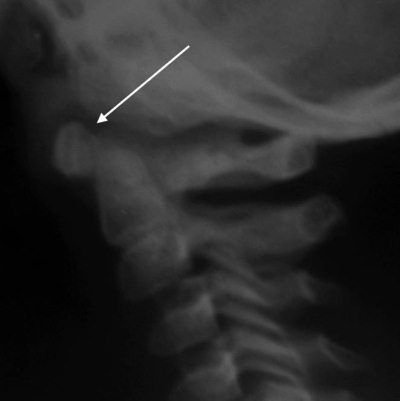

Рис. 4.11. Расширение ретрофарингеального пространства в области взрывного перелома тела CV у ребенка 15 лет (указано стрелкой)

Тень паравертебральных тканей перед телами позвонков на боковых рентгенограммах (ретрофарингеальное пространство) – показатель кровоизлияния или отека в результате травмы (рис. 4.11).

Тень до 6 мм у детей на уровне CIII вариант нормы. Для снятия подозрения на травму необходимо повторить снимок на вдохе при разгибании шеи [7].